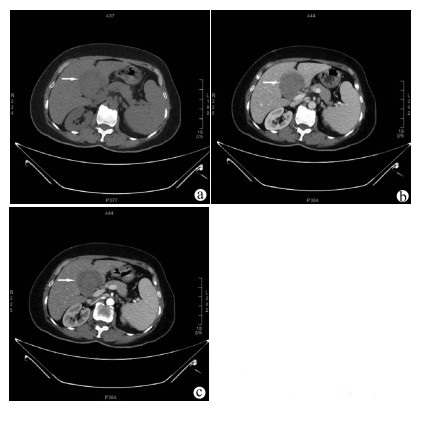

Clinical features, diagnosis, and treatment of IgG4-associated sclerosing cholangitis

Li LI, Hui LIU, Wenyan SONG

2021, 37(8): 1883-1887. DOI: 10.3969/j.issn.1001-5256.2021.08.026

Abstract(1332) HTML (583) PDF (2114KB)(94)

Abstract:

Objective  To investigate the clinical features, diagnosis, and treatment of IgG4-associated sclerosing cholangitis (IgG4-SC).  Methods  A retrospective analysis was performed for the clinical data of 25 patients who were diagnosed with IgG4-SC in Beijing YouAn Hospital, Capital Medical University, from January 2014 to September 2020, and an electronic medical record system was used to collect general information, medical history, diagnosis and treatment processes, laboratory examination, imaging data, and pathological data. Clinical features, process of confirmed diagnosis, and cause of misdiagnosis were analyzed. Normally distributed continuous data were expressed as mean±SD, and the non-normally distributed continuous data were expressed as M(Pminimum value-Pmaximum value).  Results  Among the 25 patients with IgG4-SC, there were 21 (84%) male patients, and the mean age was 57.61±9.73 years. Common initial symptoms included jaundice and/or yellow urine in 18 patients (78.26%) and weakness in 9 patients (39.13%). As for imaging classification, 16 patients (64%) had type Ⅰ IgG4-SC, no patient had type Ⅱa IgG4-SC, 4 (16%) had IIb IgG4-SC, 1 (4%) had type Ⅲ IgG4-SC, and 4 (16%) had type Ⅳ IgG4-SC. Pancreatic involvement was observed in 22 patients (88%). Glucocorticoids were the main treatment method, and total bilirubin achieved a mean reduction of 67.48% within 2 weeks. Among the 22 patients with a confirmed diagnosis in our hospital, 15 (68.18%) were suspected of "space-occupying lesions in the pancreatic and biliary system" and 5 (22.73%) were suspected of obstructive jaundice at the outpatient service. Understanding of IgG4-SC was achieved by postoperative pathology in the early stage, then imaging doctors gradually became aware of this disease, and finally multidisciplinary consultation made more physicians understand the disease, which helped to make a confirmed diagnosis earlier.  Conclusion  For patients with obstructive jaundice, clinical physicians need to identify IgG4-SC based on clinical manifestations and especially imaging features. Multidisciplinary consultation involving imaging and pathology plays an important role in helping clinicians understand this disease and making a confirmed diagnosis.